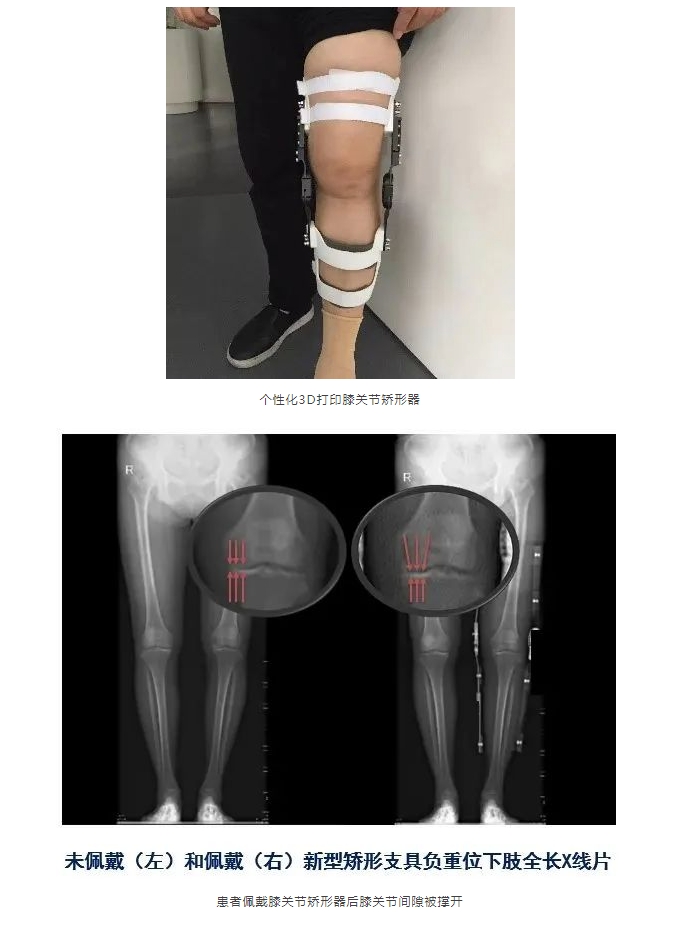

• 3D打印矫形器

新闻媒体 > 医学科普 > 膝骨关节炎的力学和炎症治疗

膝骨关节炎的力学和炎症治疗